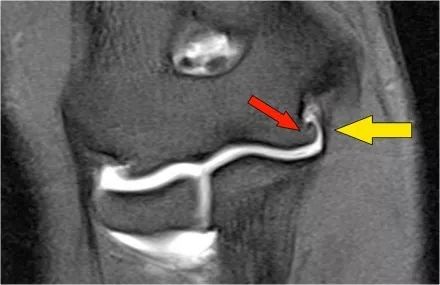

冠状图像上有一个美丽的UCL前束,但注意到关节内侧部分有骨赘形成(红色箭头)。当我们按照顺序向下看,可以看到存在一小部分低信号强度(黄色箭头),这是UCL的一部分撕裂。

这是在X线片可以更好地观察(黄箭头 )。